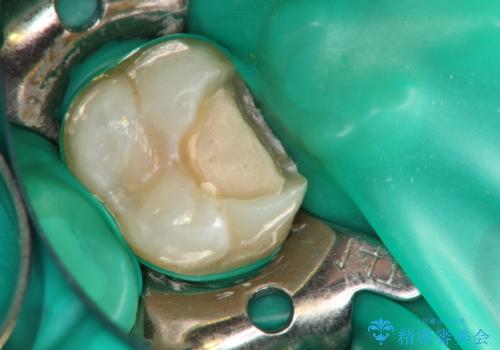

Bio-C Sealerを塗布後、神経に優しい光重合型充填用レジン強化グラスアイオノマーセメントで裏層を行っています。

※術前に神経の状態の検査を行い、術中にもマイクロスコープにて神経の状態を直接確認したうえで残せると判断した場合に行っています。

術中は唾液が入らないようラバーダムシートをかけています。